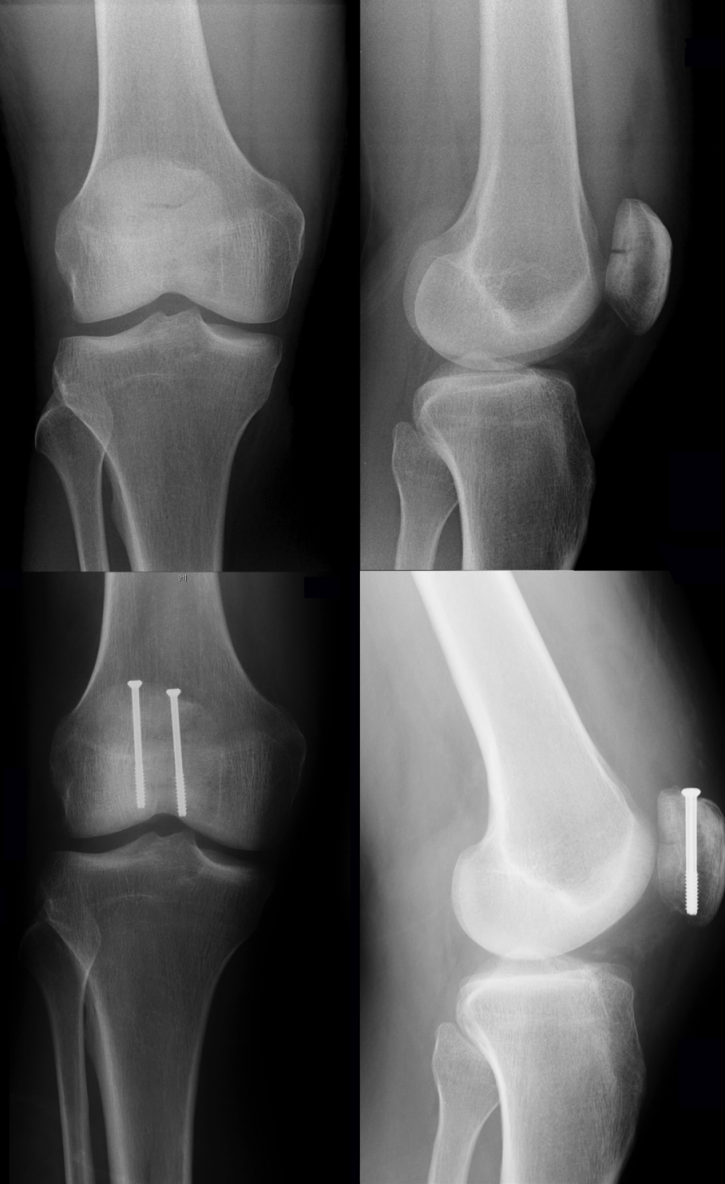

髌骨骨折术后最常见的并发症为关节活动度(ROM)下降。感染、术后长期制动及康复不当是主要诱因。在手术治疗的髌骨骨折病例中,复位丢失的发生率可达20%(图6)

图6:髌骨横向骨折术前X线片(上图)。术后3个月出现复位丢失伴螺钉拔出(中图)。翻修术后3个月采用螺钉固定联合张力带固定(下图)